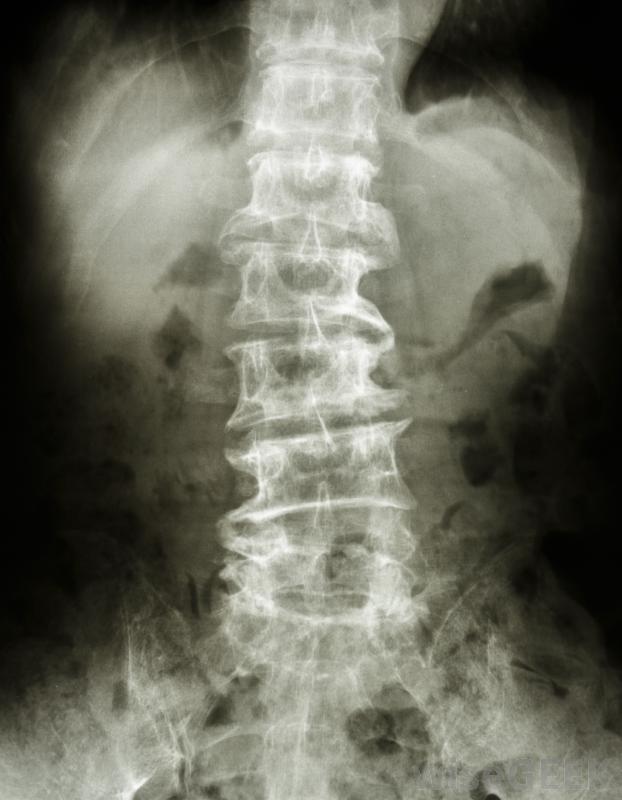

什么是椎體切除術(Corpectomy)?

椎體切除術是一種外科手術,外科醫生切除骨頭和椎間盤,以減輕病人脊髓和神經的壓力。作為手術的一部分,醫生會切除一部分構成脊柱的骨段,以及與被切除的骨段相鄰的椎間盤,以防止骨骼相互摩擦。為了填補骨和椎間盤切除后留下的空間,外科醫生使用骨移植重建脊柱,這是一種用其他骨或骨替代物替換缺失骨組織的手術。患者在椎體切除術后可能會出現喉嚨痛此手術可用于治療因骨刺導致頸椎管狹窄的患者,但它也可以在脊柱的其他部位進行,也可以用于治療其他疾病。頸椎椎管位于頸部,是脊髓穿過的通道。也被稱為骨贅,骨刺是從正常骨邊緣發育并突出的骨段,當它們接觸時伴隨著神經和其他骨骼,會引起疼痛、麻木、刺痛等癥狀,有些人還會因為頸椎椎管狹窄而出現針扎感、手臂和手部無力等癥狀,嚴重者還可能失去對膀胱和腸道的控制,難以維持平衡在椎體切除術中,患者將處于全身麻醉狀態,不會感到疼痛。椎體切除術通常是在全身麻醉下進行的,患者無法感覺到手術。當病人仰臥時,外科醫生在病人的頸部開一個小切口,開始椎體切除術。如果病人自身的部分骨組織用于植骨,可能需要另一個切口。然后,外科醫生取出要取出的骨頭上下的椎間盤,最后,外科醫生用植骨填充空隙,支撐脊柱;有時金屬板和螺釘用于額外支撐。位于頸部,即頸部椎管是貫穿脊髓的結構。椎體切除術后,有些人會感到輕微的疼痛或不適,但口服止痛藥有助于緩解疼痛。有些病人在手術后也會出現暫時性的喉嚨痛。住院康復時間不長,病人通常在手術后一兩天內出院。有些病人的癥狀可能會立即緩解,而另一些人則會注意到逐漸好轉在癥狀上值得注意的是,吸煙可能會影響術后最佳的骨愈合。椎體切除術是一種外科手術,外科醫生切除骨和椎間盤,以減輕患者的壓力脊髓和神經。椎體切除術后吸煙會干擾愈合過程出現骨突可使人的椎管變窄。